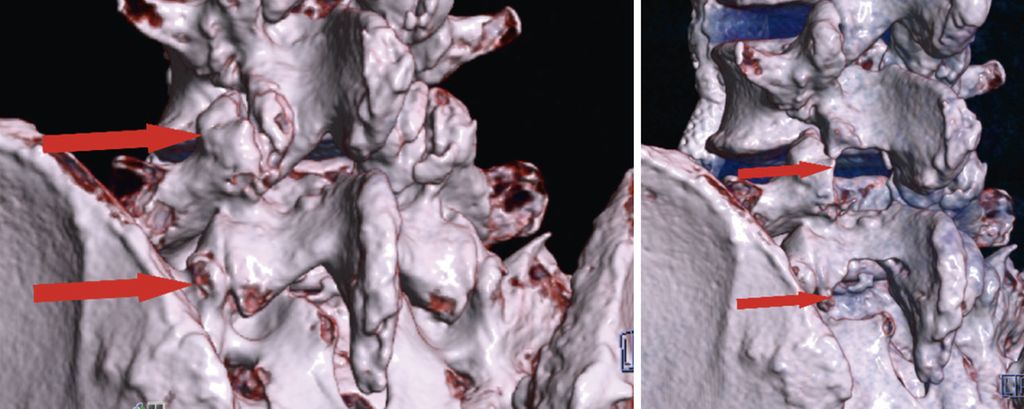

Bei zentraler Spinalkanalstenose und lateraler Rezessusstenose ermöglichen endoskopische Verfahren eine schonende und effektive Dekompression. Eingriffe können unilateral oder bilateral über die Over-the-top-Technik (ULBD) erfolgen. Randomisierte Studien belegen ein funktionell gleichwertiges Outcome im Vergleich zur offenen Dekompression, jedoch bei günstigerem Risikoprofil, kürzerem stationärem Aufenthalt und früherer Mobilisierung.13,19 Bei 161 Patienten mit lateraler Rezessusstenose konnte eine Überlegenheit der vollendoskopischen Operation hinsichtlich Operationszeit, Blutverlust, Komplikationsrate und Revisionshäufigkeit demonstriert werden.19 Am eigenen Patientenkollektiv bei 80 interlaminären vollendoskopischen Dekompressionen konnten 76% der Patienten bereits am Operationstag mobilisiert werden. Über die generellen Vorteile der spinalen Endoskopie hinaus zeigt sich, dass bestimmte Patientengruppen in besonderem Maße profitieren. Hierzu zählen adipöse Patienten, (Leistungs-)Sportler mit dem Bedürfnis nach rascher funktioneller Erholung und minimiertem Gewebetrauma sowie ältere Patienten, bei denen eine erhöhte Invasivität die Mobilisierung weiter einschränken würde und die dadurch profitieren. Abbildung 5 zeigt eine präoperative (linkes Bild) und postoperative (rechtes Bild) 3D-CT-Rekonstruktion nach endoskopischer unilateraler Laminotomie mit bilateraler Dekompression (ULBD) bei L4/5 und L5/S1 (Abb. 5).